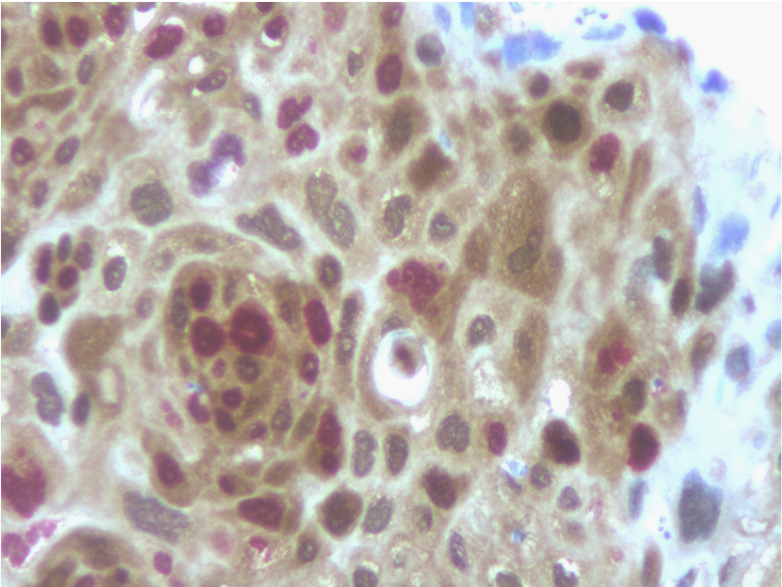

p16INK4a immunohistochemical distribution according to clinical and Histopathological findings is summarized in (Table 2). Overall, 18 of 73 cases (25%) were positive for p16 expression, assessed by the dual-staining (p16/Ki-67) immunoreaction. Positive dual-staining immunoreactivity was found only in carcinomatous cells and was mainly observed in neoplastic nests (Figure 1).

Figure 1 Detection of p16 expression (brown cytoplasmic staining) and the additional staining for the Ki-67 proliferation marker (nuclear red staining) within the same cell was regarded as a positive test result (immunoperoxidase, x400, original magnification).